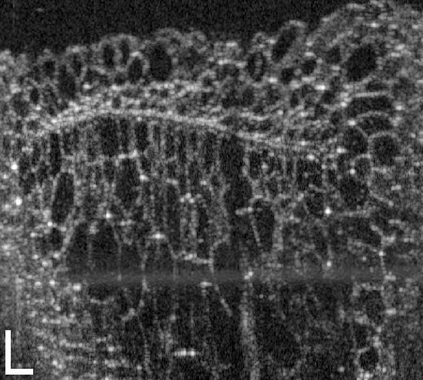

The statistical supervised learning framework assumes an input-output set with a joint probability distribution that is reliably represented by the training dataset. The learner is then required to output a prediction rule learned from the training dataset's input-output pairs. In this work, we provide meaningful insights into the asymptotic equipartition property (AEP) \citep{Shannon:1948} in the context of machine learning, and illuminate some of its potential ramifications for few-shot learning. We provide theoretical guarantees for reliable learning under the information-theoretic AEP, and for the generalization error with respect to the sample size. We then focus on a highly efficient recurrent neural net (RNN) framework and propose a reduced-entropy algorithm for few-shot learning. We also propose a mathematical intuition for the RNN as an approximation of a sparse coding solver. We verify the applicability, robustness, and computational efficiency of the proposed approach with image deblurring and optical coherence tomography (OCT) speckle suppression. Our experimental results demonstrate significant potential for improving learning models' sample efficiency, generalization, and time complexity, that can therefore be leveraged for practical real-time applications.